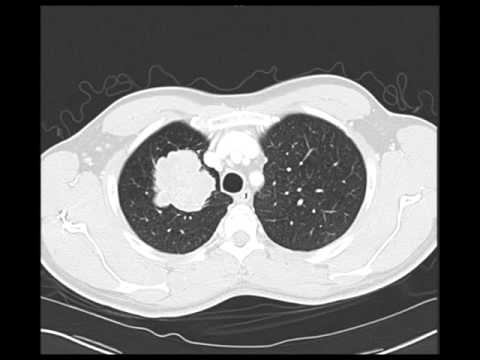

Chest Ct Scan Showing A Central Left Sided Lung Cancer With Suspected Download Scientific Diagram

Chest Ct Scan Showing Lung Cancer

Chest Ct Scan Primary Lung Cancer In The Left Upper Lobe Arrow Download Scientific Diagram